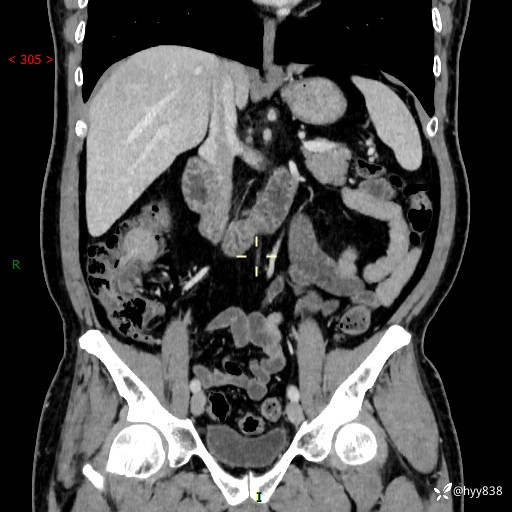

腹部CT增强扫描(外院CT平扫)

两期CT值:75hu 82hu